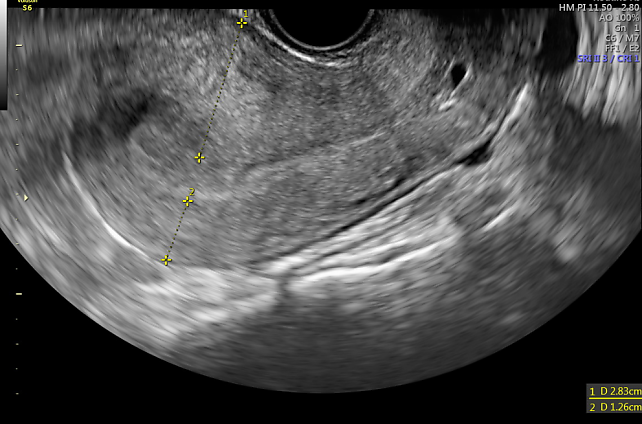

3

Ultrasound image showing asymmetry between the anterior and posterior myometrium and an irregular junctional zone. This is indicative of moderately diffuse adenomyosis, Type 1–2.